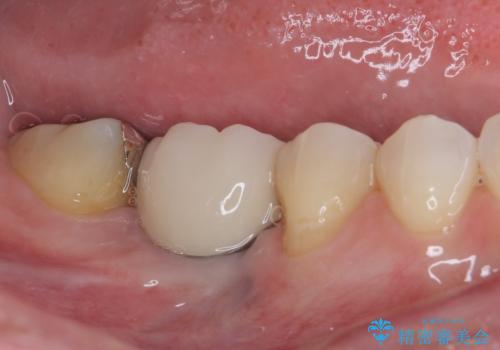

左上の奥歯のブリッジや前歯のセラミッククラウンはいったん除去し、矯正治療後に補綴治療を行うこととしました。

また、右下の抜歯が必要な奥歯は、矯正治療の途中でインプラントを埋入し、矯正治療後に上顎と合わせて補綴治療を行うこととしました。